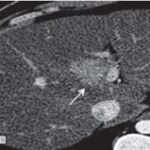

Hepatocarcinoma fibrolamelar

El carcinoma fibromelar hepatocelular es poco frecuente y representa menos de 1% de todos los casos. Se presenta principalmente en adolescentes y adultos jóvenes como una masa tumoral hepática única, con frecuencia de gran tamaño, sin asociación con cirrosis y rodeada de una cápsula fibrosa. En la tomografía multicorte, sin contraste, se observan tumores hipodensos heterogéneos con una cicatriz central muy hipodensa. También puede haber áreas de necrosis y calcificaciones. Son lesiones hipervasculares con captación intensa pero heterogénea (Anexo 15) del medio de contraste en fase arterial, la captación en fase portal y de equilibrio son variables y la cicatriz central, los septos y la cápsula del tumor son hiperdensos en fase tardía, incluyendo en los estudios de RM.(18-19)